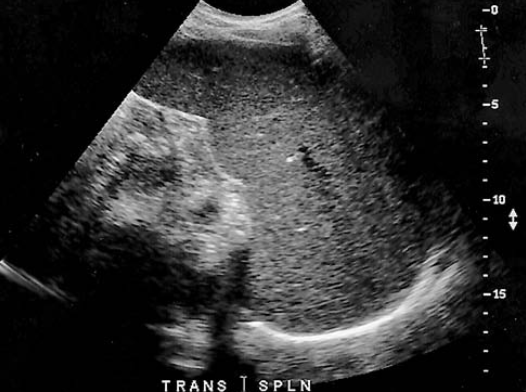

a patient presents with history of alcohol abuse. Which splenic pathology is most likely identified here

splenomegaly